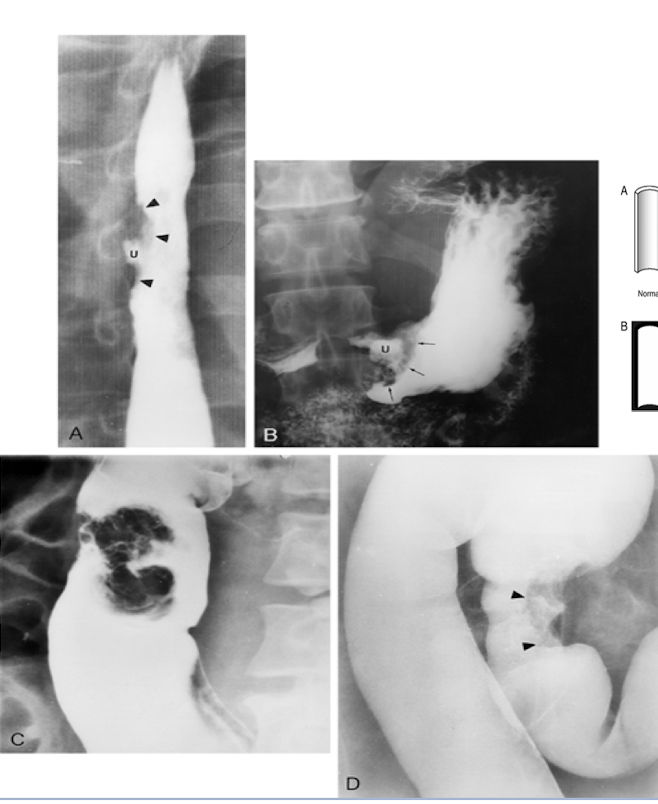

What is observed on the double contrast study in the GI tract?

a. Mucosal mass

b. Diverticula

c. Pedunculated polyp

d. Sessile polyp

c. Pedunculated polyp - wide stalk

What is shown on the imaging?

a. Mucosal mass - apple core or napkin ring

What is D?